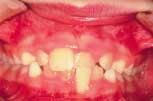

• Anterior crossbites are detrimental to a child's dental health and may need to be treated early to prevent future problems and allow for proper function and development. (Figure 1)